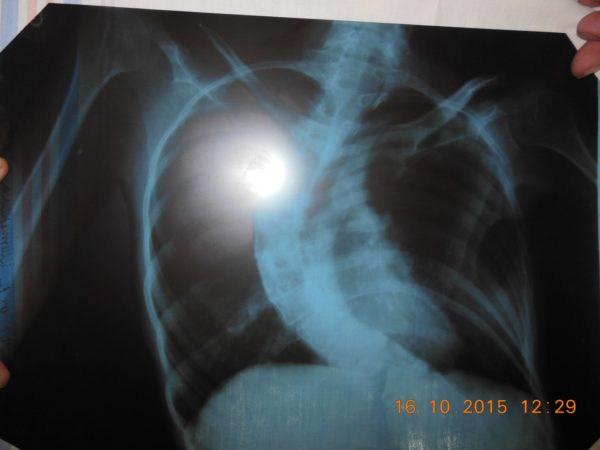

И еще Юля рассказывает, как она разыскала в Москве доктора, который делает сложные операции: «Нет, СМА пока не лечится, но мне можно выпрямить спину». Как Юля связалась с этим доктором, как он посмотрел ее снимки и сказал, что Юлин позвоночник пока еще мобилен.

Юля рассказывает, что доктор обещал сделать операцию и вытянуть ей спину. Тогда легкие расправятся, а сердце перестанет сдавливаться. Юля сможет нормально сидеть, исчезнут пролежни. Операция подарит Юле время и иное качество жизни. Титановый имплант позволит вытянуть спину и зафиксировать ее в новом положении навсегда.